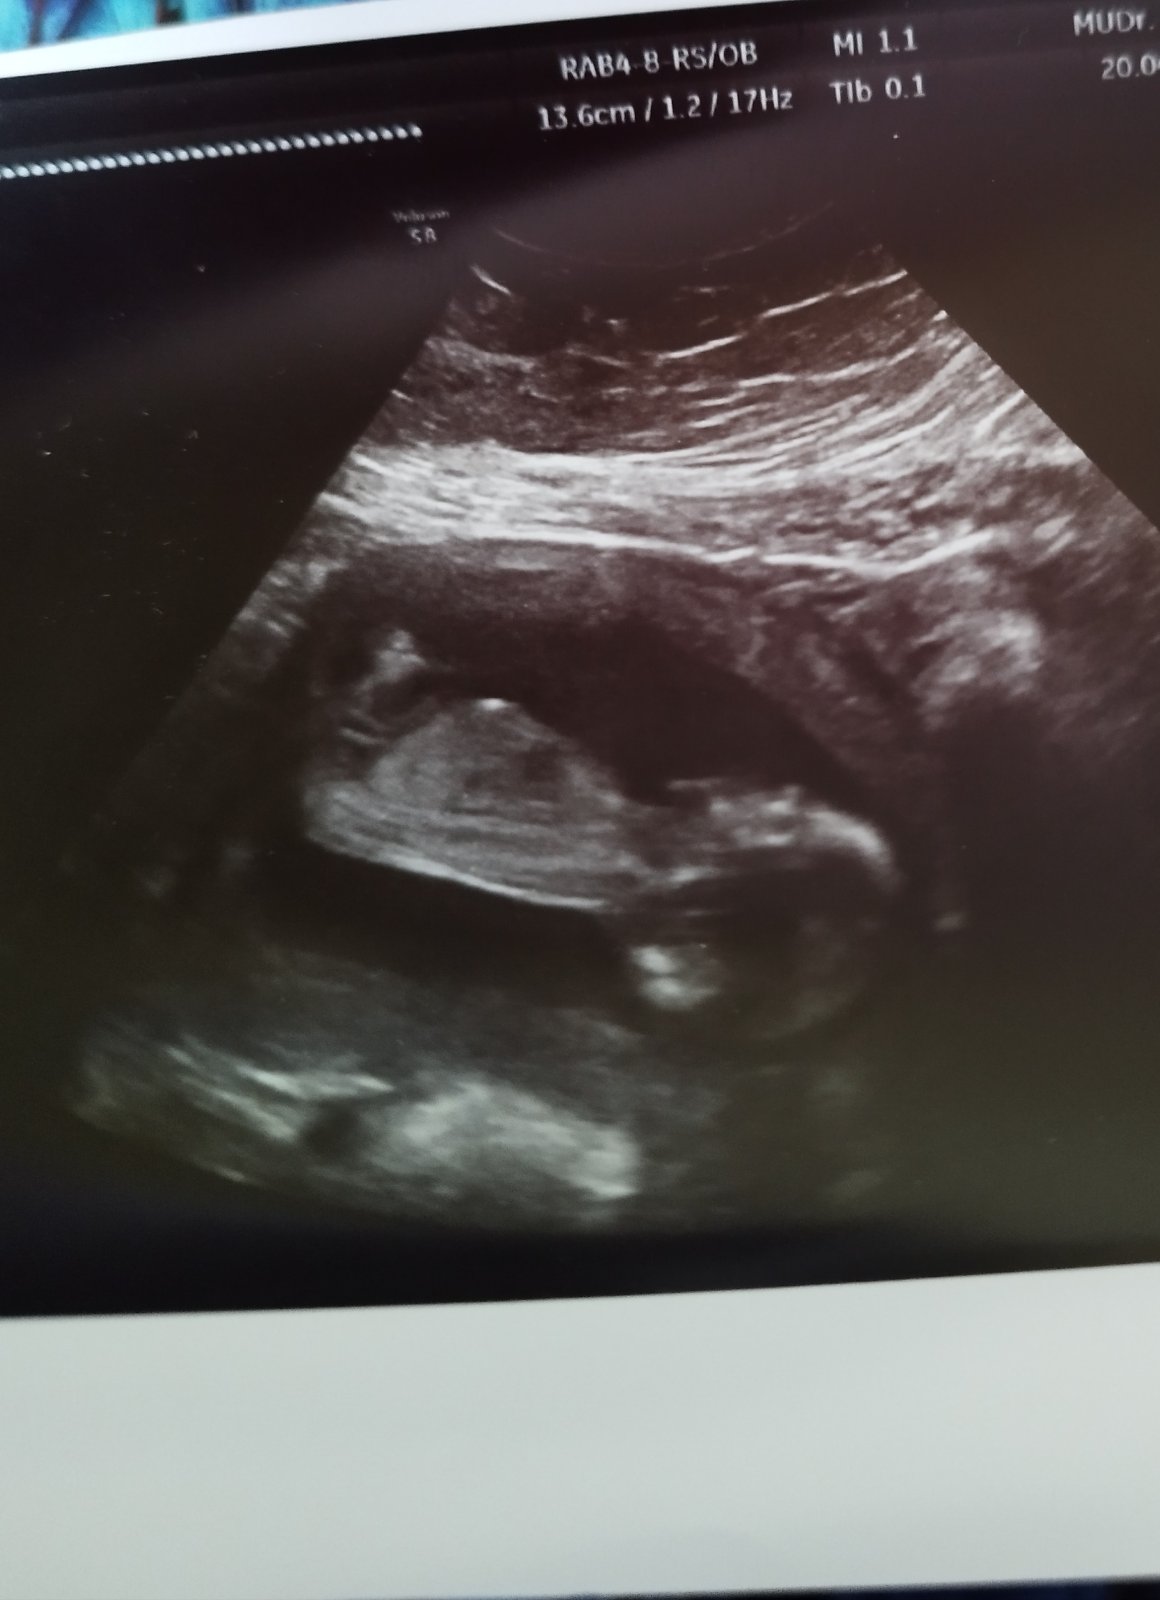

Ja si myslim,ze dievcatko... podla mna,ten falicky vybezok ide rovnomerne s osou chrbtice a aj tvsr lepky je skor gulaty ako sisaty... cisto moj typ 😇

12+4 tt ... pri prvom 11+6tt .. nemusi byt neviem aky super stroj na usg aby to dr videl, staci len dobra poloha babatka.. tí skusení dr to uz vedia podla sklonu a velkosti, mne bolo povedane, ze u dievok to az takto extra netrci a vyzera to na 80%chlapca .. ak by to predsa tak nebolo dam vam vediet 😀

@zojeva aký názor? Pohlavie nevidieť keďže je to medzi nohami a tu nic nevidno